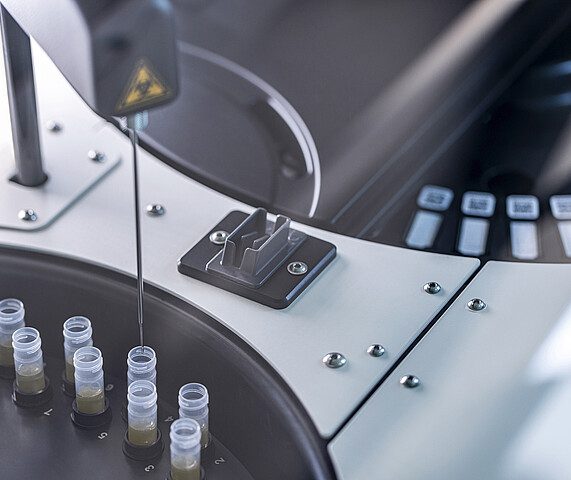

MADx: Goldstandard in der Allergiediagnostik

Mit einer kleinen Blutprobe lassen sich bis zu 300 Allergene gleichzeitig testen. Heute ist das Wiener Unternehmen in über 60 Ländern aktiv.